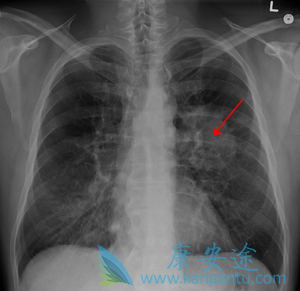

肺癌骨转移有哪些症状

肺癌骨转移是肺癌常见症状,肺癌骨转移早期尝尝被患者忽略,因为早期没有任何明显症状,到了肺癌骨转移晚期才会出现疼痛现象。

肺癌骨转移是肺癌最常见的转移部位,尤其是小细胞肺癌和分化差的非小细胞肺癌,发生率在30%左右,多发生在中轴骨,主要是脊椎骨、肋骨和骨盆骨,四肢较为少见。肺癌骨转移早期无任何临床症状,晚期出现疼痛。从产生骨转移到出现临床疼痛,往往需要1年以上时间。所以肺癌病人不可因无疼痛症状而排除骨转移,拒绝临床检查。

肺癌骨转移骨痛的特点:位置固定、疼痛逐渐加重,夜间较白天明显;胸椎转移会产生束带样疼痛;腰椎转移常发生沿下肢外侧向足外侧的放射性疼痛,随咳嗽、排便等活动加重。类似骨质增生或椎间盘脱出的坐骨神经痛,应警惕。